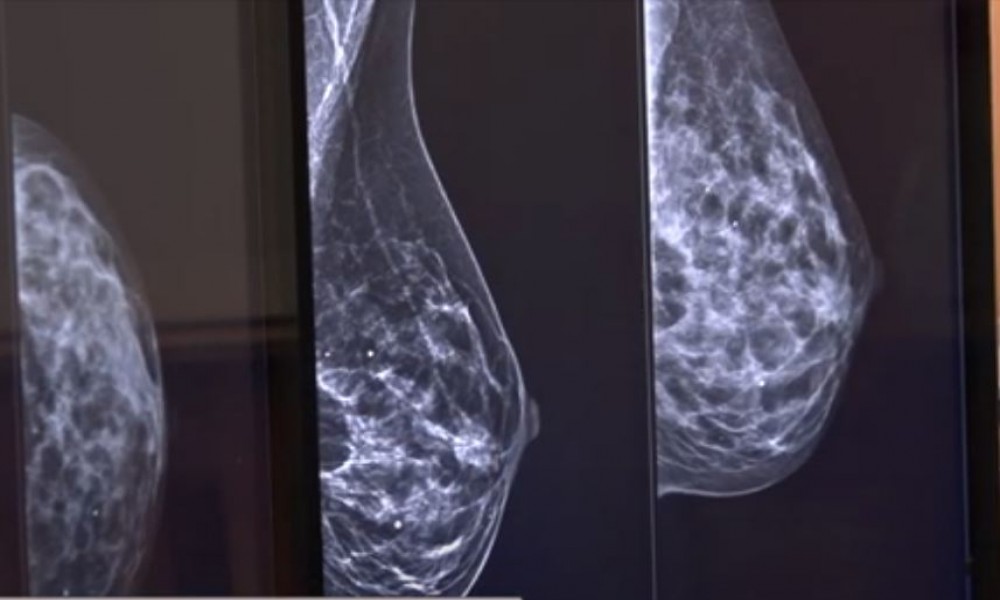

Rak dojke - najveći neprijatelj žena, važno je otkriti ga na vreme

Rak dojke je najčešće dijagnostikovano maligno oboljenje kod žena širom sveta i predstavlja najčešći maligni tumor u obolevanju i umiranju kod žena u Srbiji. U Srbiji godišnje oboli oko 4.500 žena, a rak dojke odnese više…